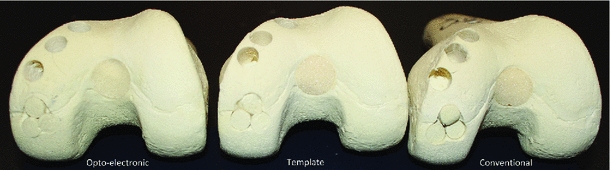

Computer intervention removes much of the human error and guesswork. My (collaborative) work has taken two forms: (1) thermoplastic custom 3D-printed templates (customized jigs), and (2) opto-electronic tracking of surgical tools.

My work showed this method to be significantly more accurate (in customized bone models) than the conventional procedure, with reduced variance. The shortcoming is that it requires a more invasive opening of the joint cavity compared to the opto-electronic method.

The other method involves attaching optical LED markers and tracking instruments using a stereoscopic camera (analogous to tracking used in motion-gaming systems, but with significantly greater reliability and accuracy). The surgical plan is overlaid on the patient’s model. The system is calibrated using 3D-printed and machined calibration blocks. Then, using an ICP-variant, the patient’s joint is registered with the computational model. The navigation system tracks instruments relative to the joint surface, providing visual feedback (6 DOF) to the surgeon.

This process is significantly more accurate than the conventional procedure and only marginally less accurate than the template method. It is more time-consuming due to calibration/registration steps, but has the advantage of being usable in less-invasive arthroscopic variants.

Validation

Sebastyan, S., Kunz, M., Stewart, A. J., & Bardana, D. D. (2015). Image-guided techniques improve accuracy of mosaic arthroplasty. International Journal of Computer Assisted Radiology and Surgery. LINKED HERE